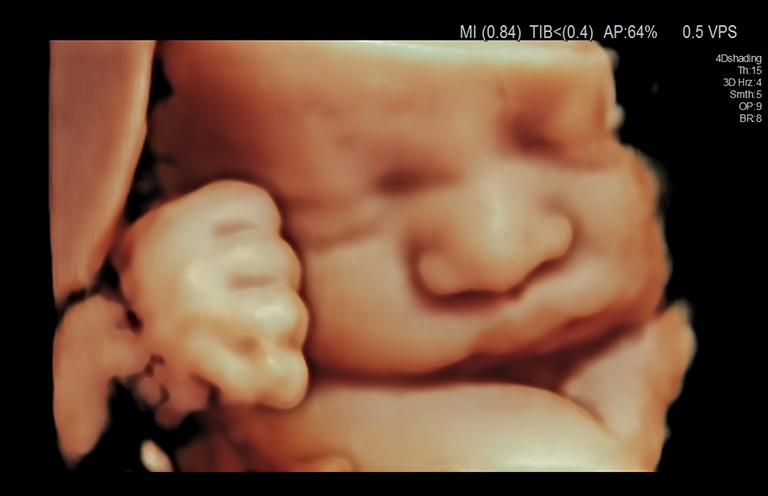

Aplicación: Obstetricia

Función/análisis: 3D/4D

Comentarios: Feto (32 semanas)